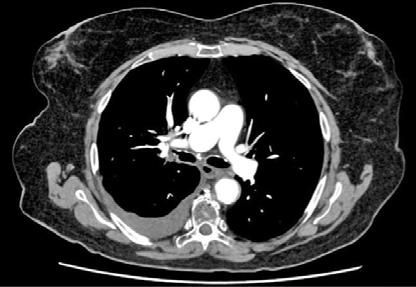

Se realizó una tomografía computarizada (TC) con contraste de forma emergente, que mostró una disección aórtica iatrogénica tipo A focal de origen en la zona 0 del cayado con extensión al tronco braquiocefálico derecho (1) sin afectar al resto de troncos supra-aórticos, cayado o aorta descendente (Figuras 1 y 2); además del hematoma

Figuras 1 y 2: Prótesis aórtica migrada y disección aórtica focal tipo A, de origen en la curvatura menor del arco aórtico (zona 0) hasta la bifurcación de la arteria braquiocefálica derecha; sin afectación de del resto de troncos supra-aórticos, del resto del cayado aórtico o de la aorta descendente.